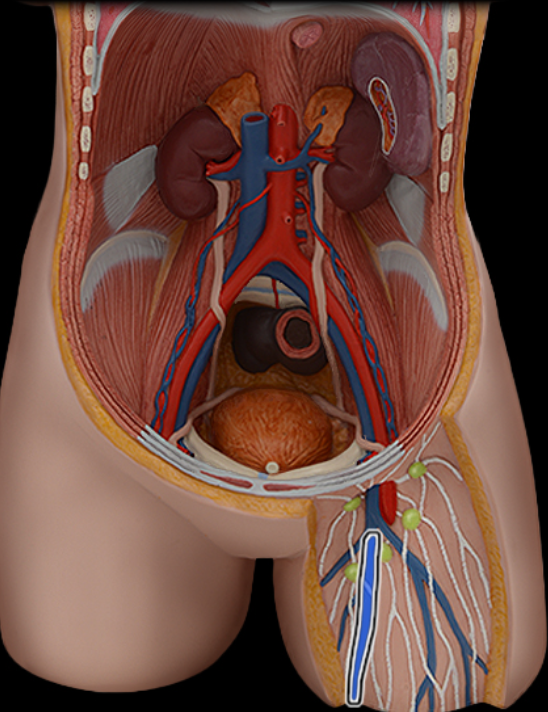

Abdominal aorta

Common iliac a.

Common iliac v.

External iliac a.

External iliac v.

Femoral a.

Femoral v.

Gonadal a.

Gonadal v.

Inferior vena cava

Lumbar a.

Lumbar v.

Renal a.

Renal v.

Superior mesenteric a.